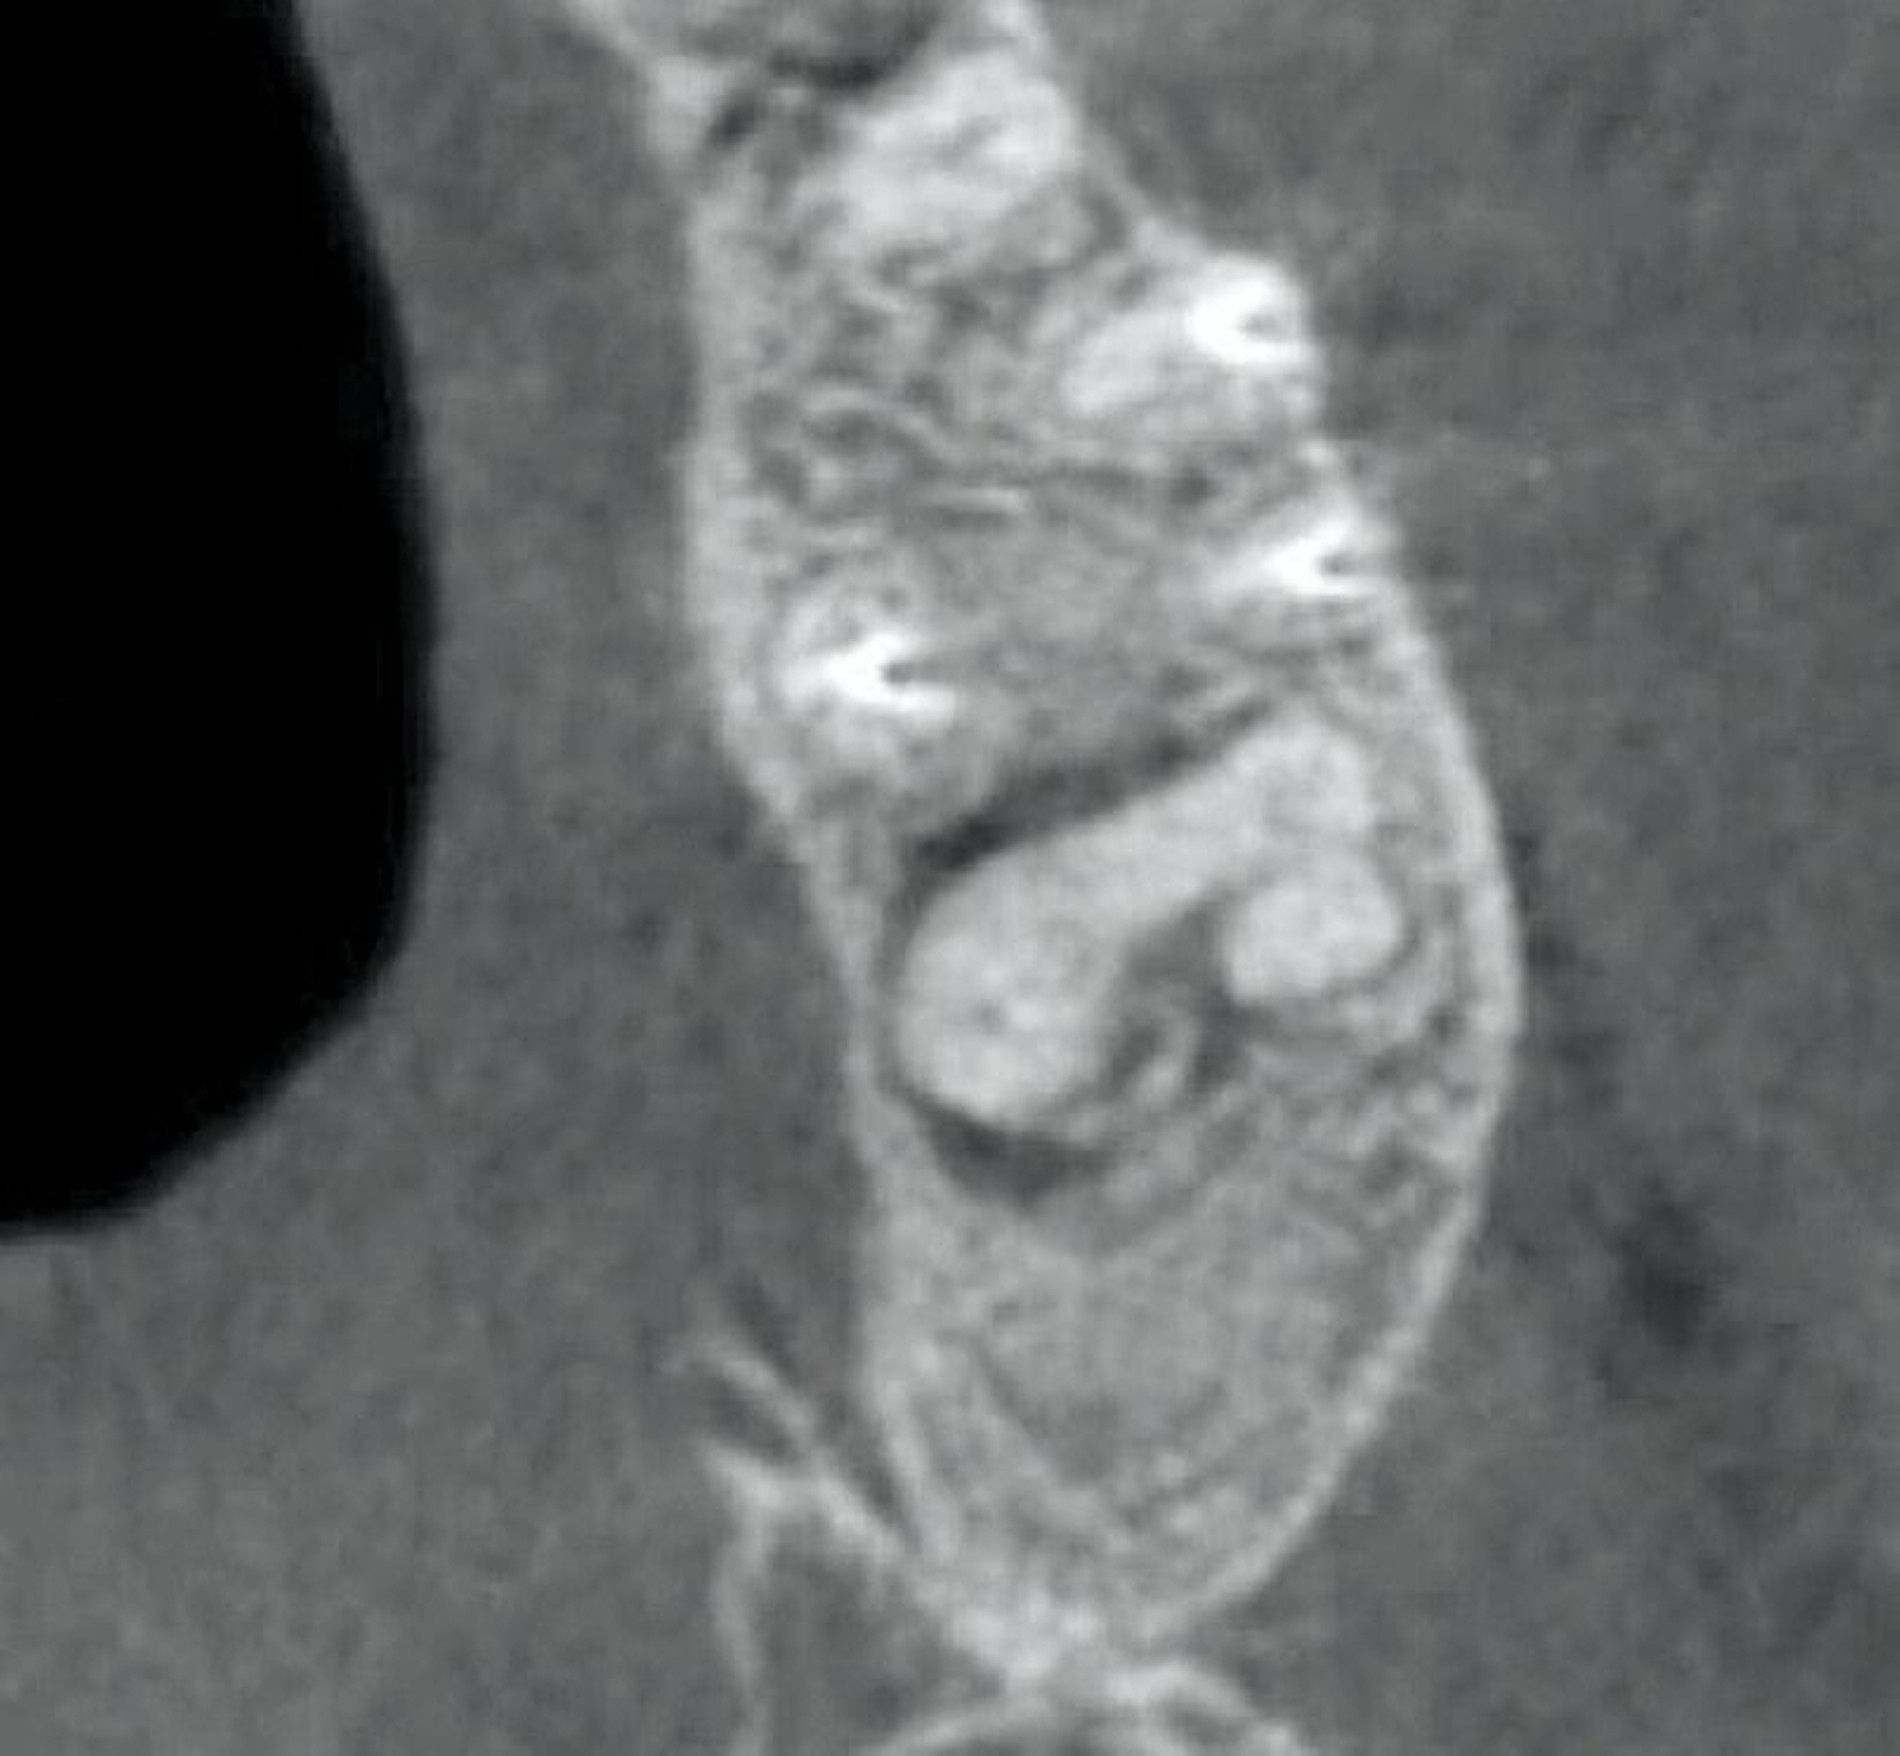

Im Februar 2022 stellte sich die 46-jährige Patientin nach Überweisung durch die Hauszahnärztin mit seit zwei Wochen bestehenden Schmerzen im linken Oberkiefer in einer MKG-chirurgischen Praxis vor. Klinisch und radiologisch zeigten sich eine tiefe Karies an Zahn 26 mit apikaler Ostitis und enger Beziehung zur Kieferhöhle (Abbildung 1) sowie der devitale Zahn 27.

Zwischen März und Oktober 2022 erfolgten dort eine Wurzelkanalbehandlung und später eine Revision an Zahn 26 sowie eine Trepanation von Zahn 27 mit Abfluss von putridem Sekret. Trotz dieser Maßnahmen blieben die Beschwerden bestehen. Ein DVT im Mai 2023 zeigte eine zystische Läsion in regio 27 mit Verdacht auf Kieferhöhlenperforation und bereits vollständiger Verschattung der linken Kieferhöhle (Abbildung 2). Zahn 27 wurde daraufhin extrahiert.